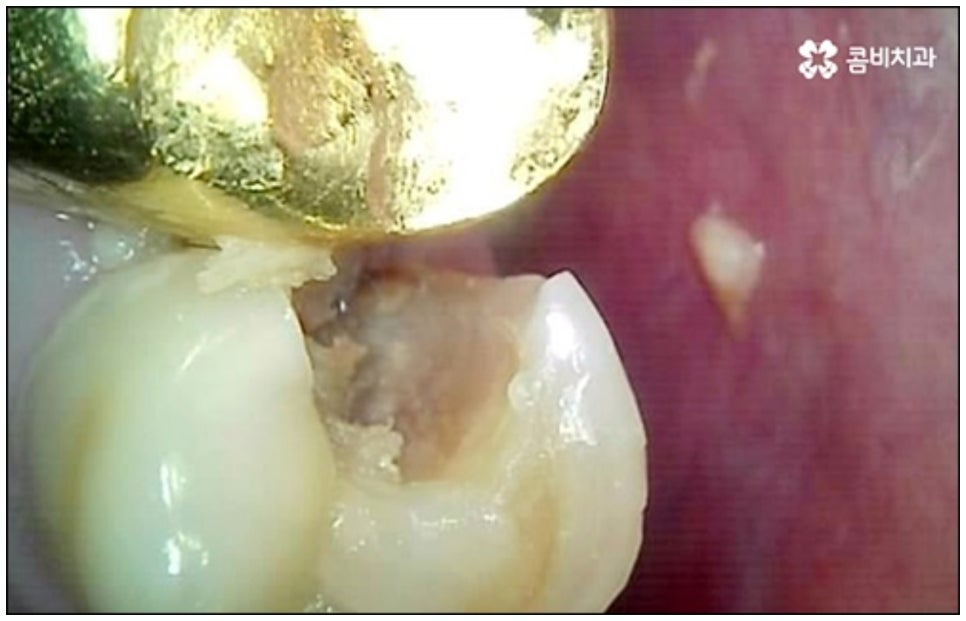

예를 들어서 오랜 치주염으로 퇴축이 진행되어 잇몸이 이미 많이 내려앉은 경우, 심한 치아 뿌리 염증으로 잇몸뼈가 상당부분 녹은 경우, 노화나 지병으로 인해 골밀도가 낮고 잇몸뼈가 약해져 지지가 어렵거나 쉽게 부서지는 등 뼈의 상태가 양호하지 못한 경우 등에 있어서는 발치 후 즉시 임플란트를 식립하는 방식이 적합하지 않으며 치아가 한꺼번에 여러개 손상된 경우에도 6~8주 정도의 시간을 두고 무리하지 않게 단계적으로 식립하는 것이 혹시 모를 부작용을 막고 장기적인 안정성을 높이는 방법이라고 할 수 있어요.

이때 당일임플란트 시술은 정밀함을 요하는 고난도 치료에 속하는 만큼 의료진의 숙련도에 영향을 많이 받기 때문에 안정적으로 골이식재가 자리잡고 식립된 임플란트가 보다 오랜 기간 강한 저작력을 견딜 수 있도록 지속력을 높이기 위해서는 다양한 환자분들의 임상 치료 경험과 뛰어난 노하우, 정확한 판단력 및 세심한 실력을 갖춘 의료진에게 시술을 받으실 필요가 있습니다.